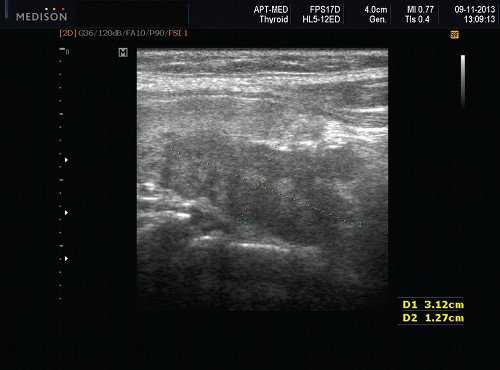

Рис. 4. Постлучевой сиаладенит.

Плеоморфная (полиморфная) аденома (смешанная опухоль СЖ) - аденома СЖ, построенная из двух типов клеток: эпителия протоков и миоэпителиоцитов. Макроморфологическая картина. Опухоль обычно представляет собой эластичный или плотный узел дольчатой серовато-белой ткани, как правило, инкапсулированный частично. Типичной для плеоморфной аденомы является так называемая хондроидная строма, напоминающая гиалиновый хрящ. Варианты эхографического изображения плеоморфных аденом представлены на рисунке 8.

Рис. 8. Плеоморфная аденома СЖ.